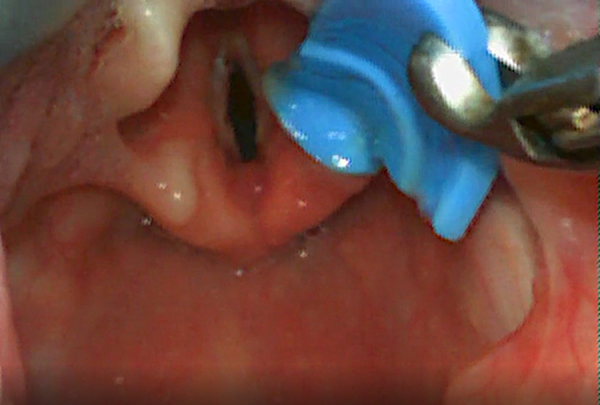

È stato questo il caso di un delicato intervento della scorsa notte al Burlo Garofolo. Un bambino di 13 mesi aveva accidentalmente ingerito un pezzo di plastica. Nel tentativo di asportazione praticato dai genitori, il corpo estraneo è stato inalato e si è incastrato al di sotto delle corde vocali. Dopo la conferma della presenza dell’oggetto al Pronto Soccorso Pediatrico di Pordenone il bambino è stato trasportato d’urgenza al “Burlo Garofolo” dove, nella notte, è stata eseguita una broncoscopia che ha consentito di asportare il corpo estraneo, come si vede nelle foto, evitando così il rischio di soffocamento.

L’equipe del Burlo era composta dai dottori Domenico Leonardo Grasso e Paola Staffa della S.C. di Otorinolaringoiatria e Audiologia (diretta dalla dott.ssa Eva Orzan), dai dott. Riccardo Pinzan e Paola Mergoni della SC di Anestesia e Rianimazione (diretta dalla dr.ssa Raffaella Sagredini) e dalle infermiere Lorena Vatovac, Alina Savulescu, Monica Pozzato e Sara Cherti. L’equipe aveva già eseguito un’altra broncoscopia nella stessa serata su un altro bambino che aveva invece inalato del cibo, confermando così la frequenza di queste pericolose evenienze.

Estrazione del corpo estraneo in broncoscopia